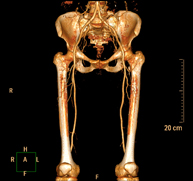

Prova diagnòstica no invasiva que consisteix en l'estudi vascular del sector aorto-ilíac i dels vasos arterials d'ambdues extremitats inferiors i l'obtenció d'imatges d'alta definició anatòmica mitjançant l'ús d'un equip de TC Multidetector d'última generació i de contrast iodat. La qualitat de les imatges permet realitzar reconstruccions en 2D i 3D gràcies a estacions de treball especialitzades en l'estudi arterial.

- Lower leg arterial CT angiography

Non-invasive diagnostic test consisting of a vascular study of the aorto-iliac sector and the arterial vessels of both lower extremities, obtaining high-definition anatomical images using state-of-the-art multidetector CT equipment and iodinated contrast. With the aid of workstations specialised for arterial studies, the image quality supports 2D and 3D reconstructions.